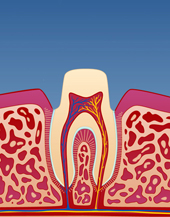

Fyllingsterapi

I mange tilfeller kan en knekt tann repareres med en tannfylling. Man vil først fjerne den gamle fyllingen i tannen og deretter bygge opp med en tannfarget fylling i plast (kompositt).